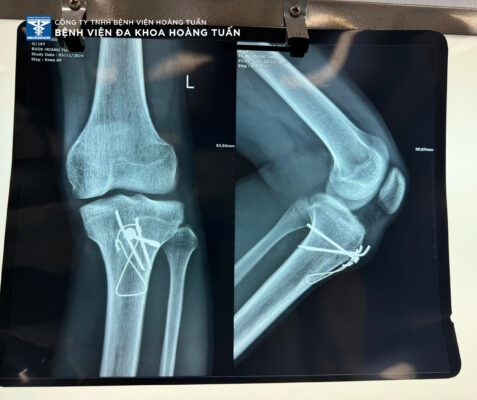

Việc tháo dụng cụ kết hợp xương (như nẹp, vít, tấm kim loại, hay khung cố định) là một quy trình phẫu thuật cần được thực hiện bởi bác sĩ chuyên môn. Quy trình này thường xảy ra khi xương đã lành và ổn định, và dụng cụ không còn cần thiết nữa. Mục đích của việc tháo dụng cụ là giúp bệnh nhân giảm đau, cải thiện sự vận động và tránh các biến chứng như viêm nhiễm, kích ứng hoặc tổn thương mô mềm. Quy trình tháo dụng cụ kết hợp xương thường bao gồm các bước sau:

- Thực hiện phẫu thuật: Bác sĩ sẽ rạch một vết mổ nhỏ để tiếp cận dụng cụ kết hợp xương, sau đó tháo bỏ các dụng cụ như vít, nẹp, tấm kim loại.